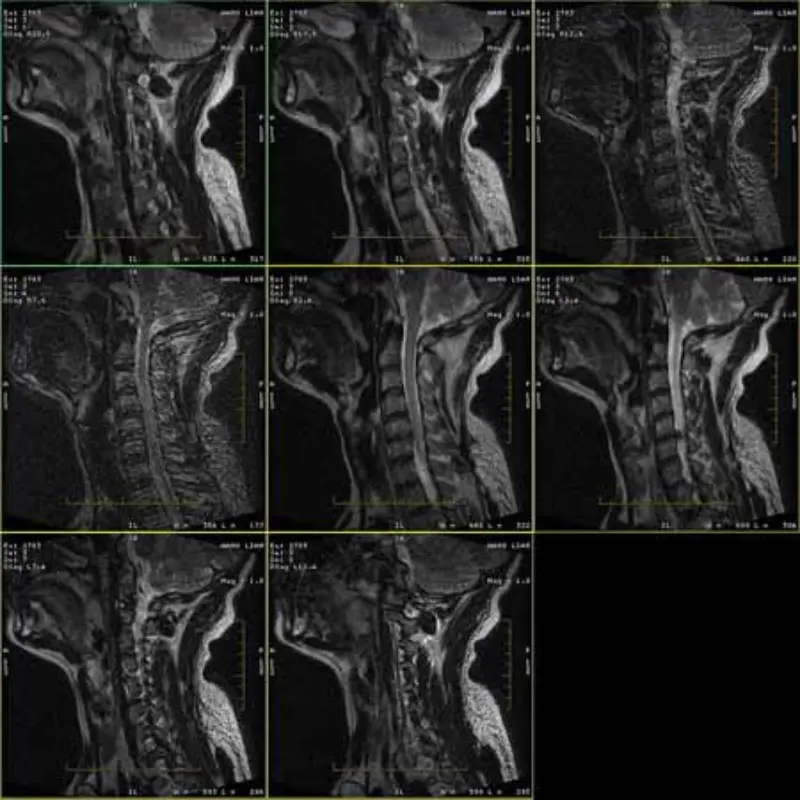

Изображенията на протоколите FRFSE и GRE имат призрак и понякога изображения с нисък SNR се появяват в една серия. Но изображенията на SE протокола са нормални.

Моля, вижте прикачени изображения.